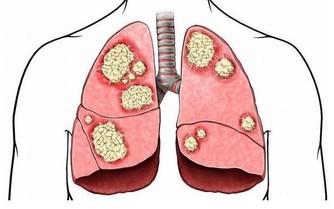

如果經常感覺到自己的嘴角有口瘡出現,而且容易全身疼痛,多半是某些重要的維生素缺乏了,特別是維生素D缺乏的時候應該高度重視。維生素D獲取充足能夠促進身體對鈣質的吸收,很多人全身疼痛,主要和鈣質缺乏有關,骨質疏鬆這種情況比較明顯,很多人就會感覺到全身產生疼痛感,甚至會有肌肉無力的感覺。

如果已經有這種現象,需要從飲食過程中獲取足夠的維生素D,平時還可以適當曬曬太陽,這樣可以促進身體對維生素D的合成,防止缺乏維生素D而出現全身疼痛表現。